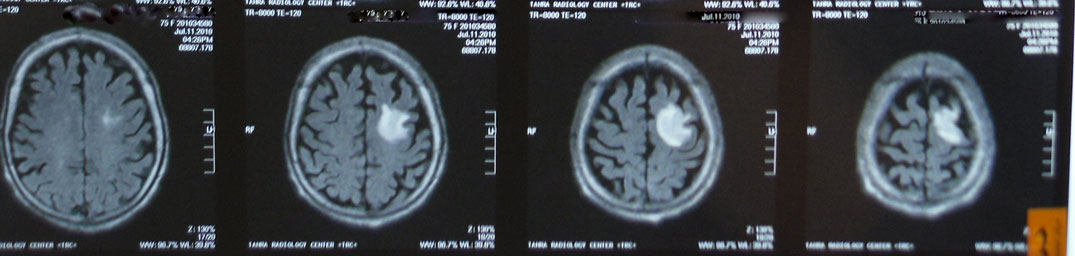

A 74 year-old female, diabetic, complained of

unilateral right upper limb fits that became generalized.

CT And MRI brain ordered with the above photos results.

Left high parietal subcortical lesion with mass effect manifested as

effacement of the adjacent sulci, mostly neoplastic mass lesion for

better assessment by enhanced MRI study.